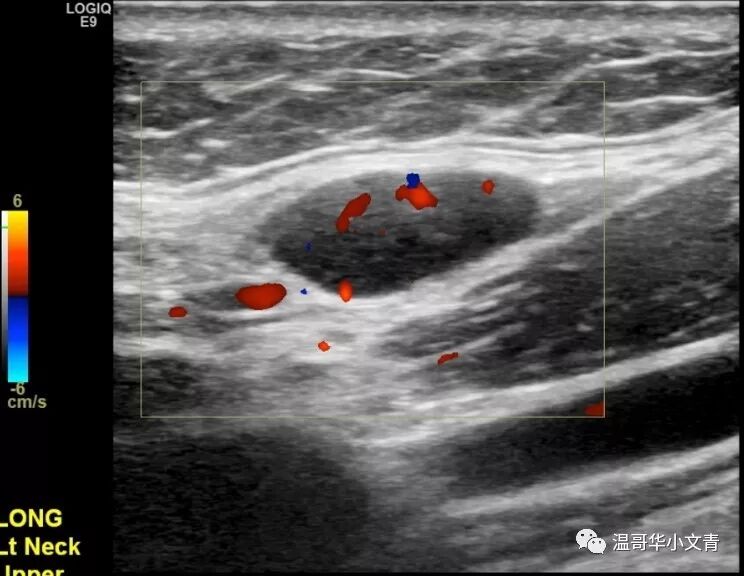

随着知识的普及,大家都知道颈部彩超检查对于甲癌病人非常重要,尤其是乳头状癌和髓样癌的病人。 经常有病友来群里吐槽: “他奶奶的,排队排了两个小时,彩超医生把探头在我脖子上晃了40秒就搞完了,真尼玛瞎搞!” “做了几个医生的彩超,各个结果都不同,真蛋疼!” 所以今天小编就和大家来讨论下彩超检查: 如何正确的进行彩超检查? 如何解读彩超结果? 彩超检查的结果有什么意义? 如何正确的进行颈部彩超检查? 这部分内容取自斯坦福医院的Lisa Orloff,她本身是头颈外科医生,也是彩超师。 术前彩超和术后彩超的操作方式是类似的。不过,术前彩超是越精确越好,术后有时候对彩超的要求反倒不需要那么高,今天主要讨论的是术前彩超。做彩超最重要的是动图,通过动图发现可疑的病灶,再逐个详细分析。Lisa推荐的检查顺序是: A 甲状腺和气管旁中央区淋巴结 (两侧) B 峡部气管前中央区淋巴结 C 喉前中央区淋巴结和声带 D 侧颈大血管周围二三四区淋巴结 (两侧) E 侧颈五区淋巴结(两侧) F 一区淋巴结以及唾液腺 当动图发现了问题之后,再把有问题的地方详细的记录下来,形成一整套图片。最后彩超医生把图片和报告交给内分泌医生或者手术医生,由他们定夺治疗方案。彩超最重要的其实是动图和图片,而不是报告上简单的几行字。 彩超结果能解读出哪些信息? 第一个是判断甲状腺结节的大小,数目和属性。如果甲状腺的结节出现微钙化,纵横比大于一,边界不清晰这些字眼,结节是恶性的可能性就比较高。一般来说拿到图片良恶性都能有个大致判断,有的时候不好判断也没关系,反正还有穿刺。 第二个是如果是甲状腺癌,判断原发肿瘤有没有侵犯周围的组织。比如说这个肿瘤是不是和气管的关系比较密切?是不是有可能侵犯了前被膜?是不是有可能侵犯了后被膜导致和喉返神经关系密切。 第三个是判断淋巴结的转移情况。大家都知道如果淋巴结出现钙化,囊性化,局部高回声基本都是转移的;如果没有淋巴结门结构,形状是圆形那么就是相对可疑的。读图比看文字描述更可靠!因为你会知道这个淋巴结到底有多可疑!或者到底有多坏! 实际上彩超在侧颈淋巴结的区域更为敏感,下面就是一些例子: 右侧颈5区的淋巴结,8毫米,不规则血流。红箭头指向的地方是微钙化,你看图就知道这是乳头状癌的转移淋巴结。 左侧颈4区的淋巴结,6毫米,不规则血流。高度怀疑是转移的淋巴结。 左侧颈3区的淋巴结,7毫米。红箭头指向的地方是钙化点,你知道这是一个乳头状癌转移淋巴结。 左侧颈2区的淋巴结,1.5厘米,没有明显的淋巴结门结构,是一个中度可疑的淋巴结。 当彩超医生阅读完所有的图片之后,就会把信息聚集起来,形成一幅肿瘤分布图,告诉内分泌或者外科医生原发肿瘤到底有多少?腺外侵犯有多少?淋巴结转移有多少?它们在哪里? 彩超检查结果有什么意义? 第一,彩超结果可以指导医生是否需要进一步的影像学检查,比如说颈部的增强CT。 大概有20%-25%的病人在彩超上有明显的转移需要颈部增强CT检查。彩超能看出来结节和气管关系密切,但是要想知道侵犯了气管的多大面积就需要增强CT;彩超能看出来常规的中央区侧颈区的淋巴结转移,但是有的病人可以转移到鼻子后面的淋巴结(咽后淋巴结),胸骨后面的淋巴结(纵隔淋巴结),这时候就需要增强CT。 第二,彩超结果可以指导放射科医生穿刺哪些部位。 一般来说,需要一个恶性证据去展开手术;另外可能影响手术方案的淋巴结也需要穿刺。 第三,彩超结果可以指导手术医生手术的方案。 手术是半切还是全切? 中央区清扫是一侧还是两侧? 侧颈区清扫不清扫,清扫多大的范围? 手术涉及不涉及气管,食道这些关键位置? ...... 第四,彩超结果可以告诉病人大概的预后。 很多人拿到彩超结果还没手术就喜欢问需要不需要碘131?有没有远转?这个确实需要一步步的来看,但是彩超的结果也是一个很好的预判。 如果你的彩超检查很详细但没有显示任何转移,你的预后是非常非常好的,你基本不可能发生远处转移,而且术后需要碘治疗的可能性很小;如果你的彩超显示有大面积的淋巴结转移,你术后基本就需要碘治疗,而且可能还需要一个胸部CT评估肺部的状况。